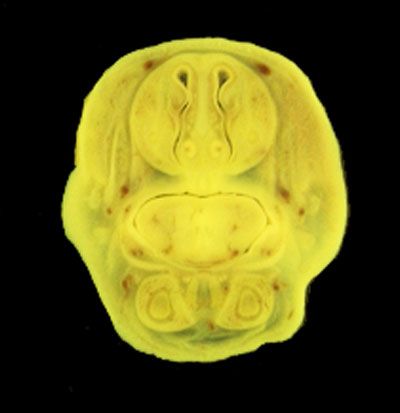

The images below show the normal appearance of Bouin's fluid fixed head sections in specimens at Day 21 of gestation (day mating observed = Day 0).

It is essential that both sides of each section is examined so that structures that exist is several sections can be visualised by the examiner in 3D.

Learning objective: Compare the diagrams with your own specimens and identify all of the structures that have been labelled.

Unlabelled Images